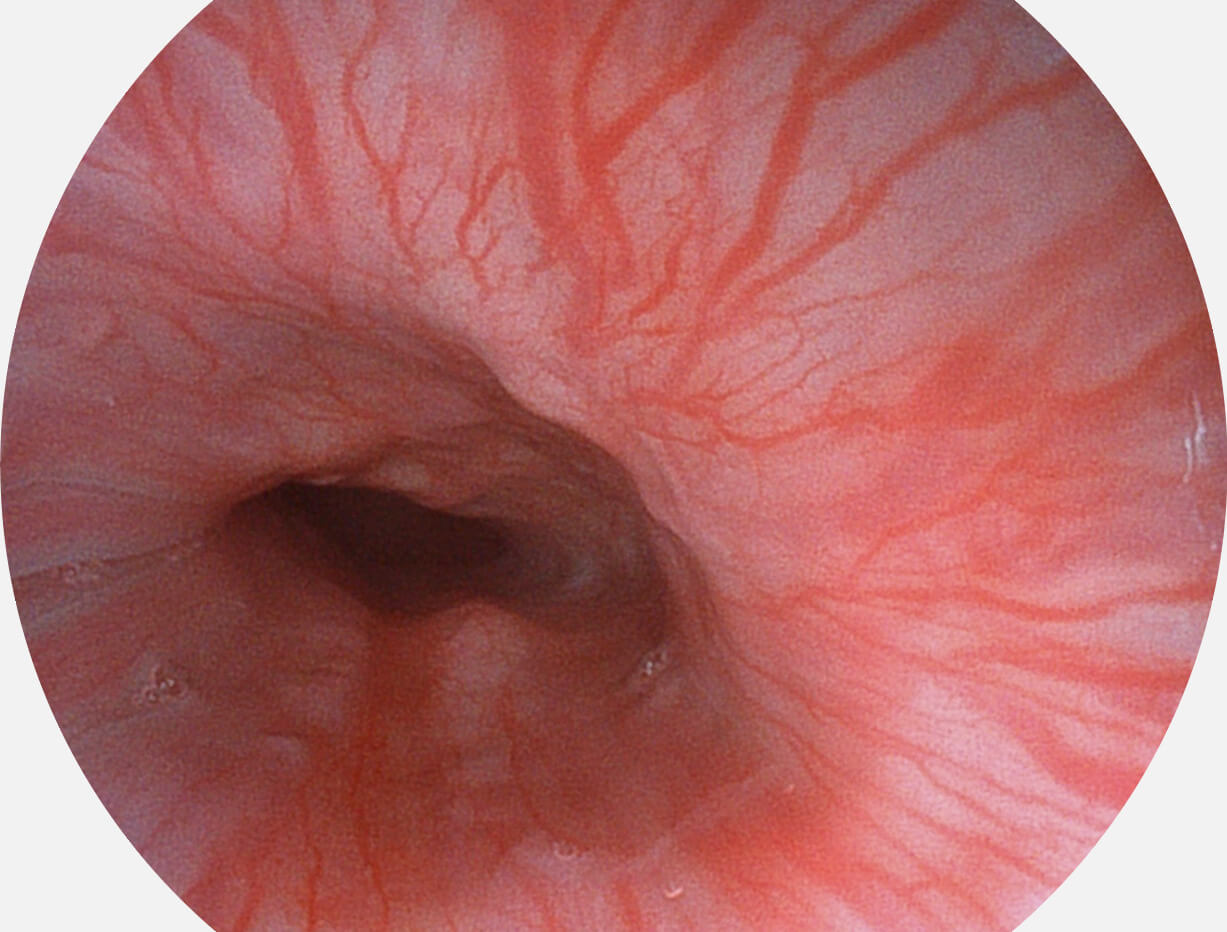

白光图像

SFI图像